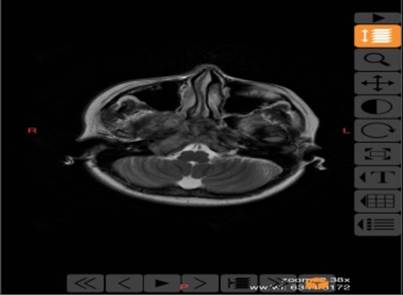

患者赵某,女性,以“间歇性剧烈头痛,右侧面瘫,声嘶”半年等症状入院,入院诊断为中颅窝、后颅窝肿瘤占位,颞下窝颈静脉孔区巨大占位。由于长期慢性消耗,体重仅剩35公斤,经耳鼻咽喉头颈外科和神经外科联合会诊认为患者不能耐受开颅路径肿瘤切除手术。耳鼻咽喉头颈外科在张少强主任、白艳霞副主任的指导下开展术前讨论并组织全院多学科MDT联合会诊,针对患者情况,制定了经鼻内镜中颅窝、后颅窝、颞下窝颈静脉孔区肿瘤切除术手术方案。

手术在赵继元副主任医师指导下,由邵渊主任医师主刀,在李化静主治医师、康伟博士、麻醉科毕阳主治医师全力配合下进行,手术经右侧鼻腔进入,首先切除咽旁间隙颞骨岩下区肿瘤,在颈静脉孔完全被肿瘤包绕的情况下,分离颈内动脉及颈内静脉并完整切除肿瘤。后以圆孔为中心进入中颅窝Meckel腔,分离斜坡段颈内动脉,切除岩上区包绕三叉神经节肿瘤及部分大脑颞叶组织,绕过岩尖到达颅后窝桥小脑角区,分离颅后窝面神经并切除窝面神经内耳道段肿瘤,用人工硬脑膜及带蒂鼻中隔黏膜瓣修补颅底缺损。

手术历时7小时顺利完成,术后患者面瘫、头痛症状完全消失,声嘶症状明显好转,精神状态和营养状况较入院初已有明显改善,转入肿瘤内科进一步治疗。经鼻内镜切除前颅底、中颅底、后颅窝肿瘤具创伤小,恢复快等优势,部分患者可以避免开颅手术,成为鼻颅底疾病的首选外科技术。